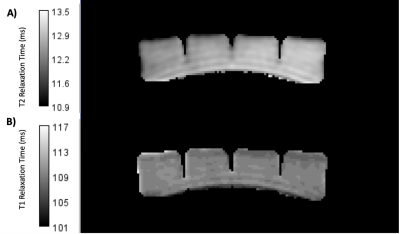

2D inversion recovery images were acquired using inversion times (TI): 50, 60, 75, 100, 200, 250, and 500 ms. T2 was characterised using a spin echo sequence with echo times (TE): 10, 15, 20, 40, 60, and 80 ms. The following imaging parameters were used for all relaxation data acquired: Number of slices=1, acquisition matrix size = 128 x 128, reconstructed matrix size= 256 x 256, slice thickness = 5 mm, field of view (FOV) = 256 mm, and bandwidth= 122 Hz/pixel. MTR values were calculated using an Enhanced Fast Gradient Echo 3D sequence (EFGRE3D) with and without a fermi magnetization transfer pulse of duration 8 ms, offset by 1200 Hz, and a flip angle of 200°. The imaging parameters of the EFGRE3D sequence were: number of slices = 86, slice thickness = 2 mm, FOV = 256 mm, acquisition matrix size = 320 x 320, bandwidth = 244 Hz/Pixel, TI = 32 ms, and TE = 2.77 ms.Voxel-wise curve fitting was performed on the resultant relaxation data to allow the creation of T1 and T2 maps respectively of the phantom in MATLAB (2022a, MathWorks, Cambridge, MA), displayed in Figure 2. Equations 1 and 2 were used for fitting the T1 and T2 data respectively, where Mxy is the signal intensity at each voxel location, and M0 is the maximum signal. MTR values for the phantom were calculated using Equation 3, where SIMTon and SIMToff are the signal intensities with the magnetization pulse turned on and off respectively.

Figure 2 - T2 (A) and T1 (B) maps generated for a block of store-bought jelly